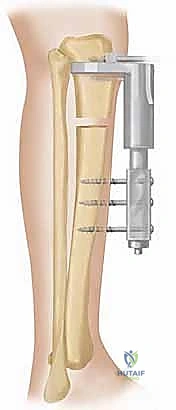

ثانياً: المثبت أحادي المستوى (The Monolateral Fixator)

هو نظام تثبيت خارجي يوضع على جانب واحد من الطرف (بدلاً من إحاطته بالكامل كالحلقات). يتكون من سكة حديدية صلبة (Rail) تُثبت في العظم باستخدام مسامير معدنية سميكة (Schanz pins).

مميزات المثبت أحادي المستوى:

* راحة أكبر للمريض: لعدم وجود حلقات تحيط بالكامل بالطرف، مما يسهل ارتداء الملابس والنوم.

* سهولة الاستخدام: عملية الشد والتطويل تكون أسهل للمريض عبر مفتاح مخصص على السكة الجانبية.

* مثالي للتطويل المباشر: يُستخدم بكفاءة عالية في حالات القصر التي لا يصاحبها تشوهات زاوية أو دورانية معقدة.